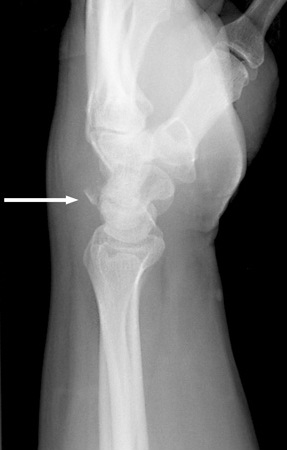

Triquetrum fracture

- Lateral/oblique in partial pronation

- Best for seeing avulsion fracture (tiny flake of bone on dorsum of triquetrum)

- PA

- Best for seeing nondisplaced fracture